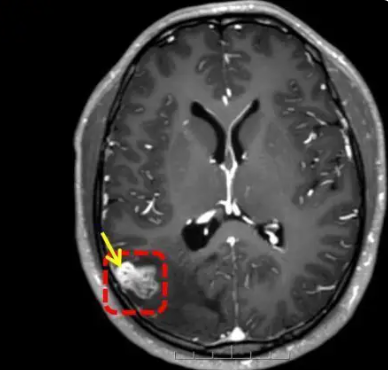

Upon further investigations, which included an MRI, doctors found a foreign object inside his brain.

Source: QQ News

Initially, it was unclear what the object was, but they soon discovered that it was an 18cm-long parasitic worm, specifically, a Taenia solium, also known as a pork tapeworm.